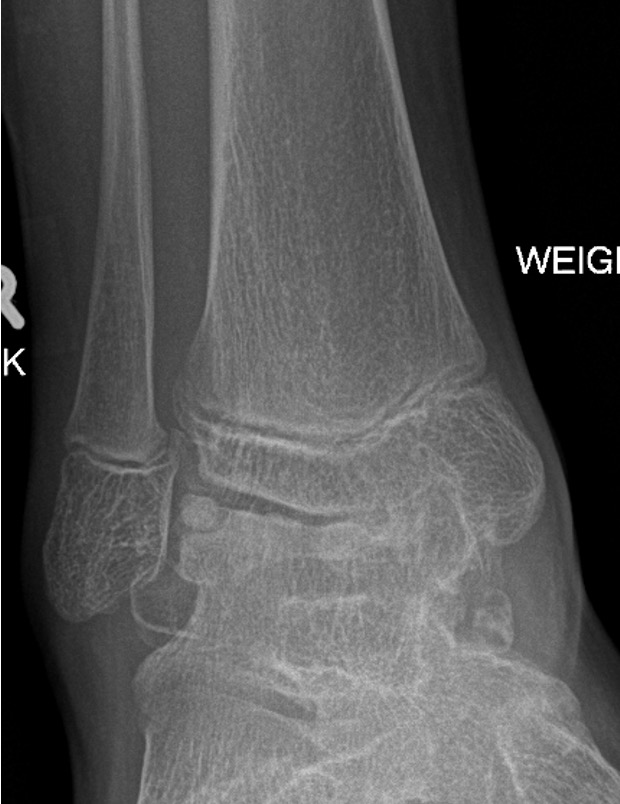

Ankle

- valgus

- fibular shortening with valgus distal tibia

- wedge-shaped distal tibial epiphysis

- leads to valgus talar tilt in abnormal mortise